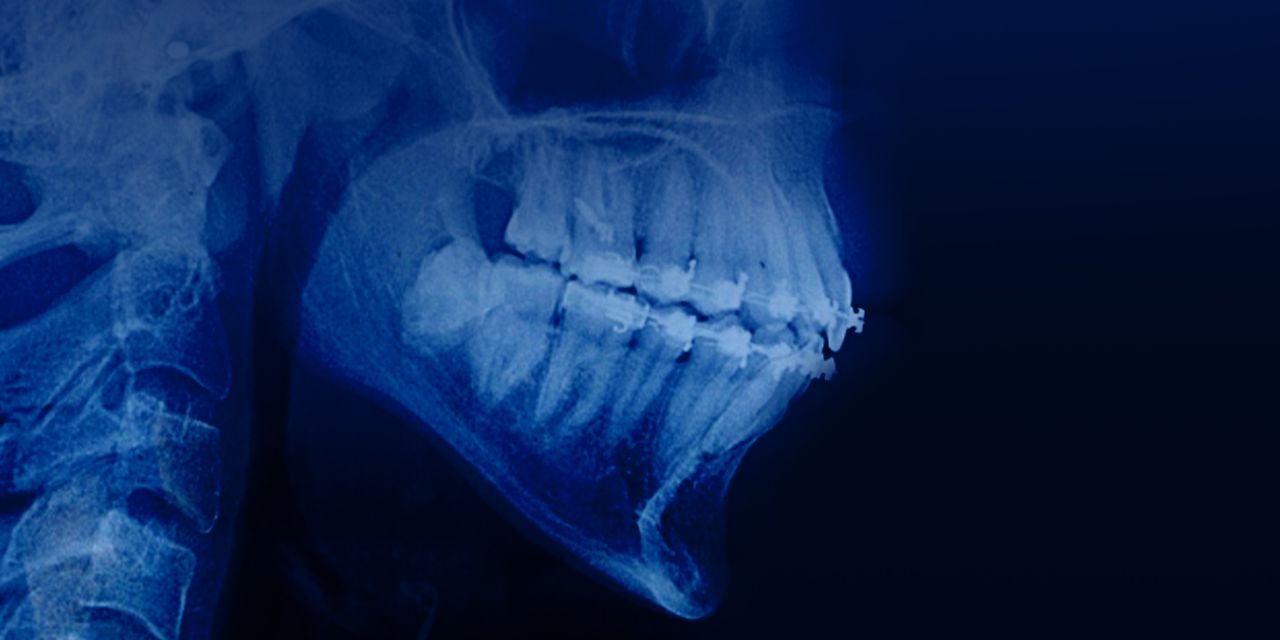

Лечение взрослых пациентов с открытым прикусом и вертикальным типом роста

– Диагностика вертикального типа роста

– Морфология лица: клинические признаки удлиненного лица

– Этиологические факторы вертикального типа роста и открытого прикуса

– Контроль вертикального размера: значение и тактика

– Оценка ортодонтического лечения пациента с вертикальным типом роста

– Сегментарная механика: вариант вертикального контроля

– Протокол лечения взрослых пациентов с вертикальным типом роста

– Применение микроимплантов в боковом сегменте для интрузии

– Авторотация нижней челюсти

– Хирургическое вмешательство: показания.